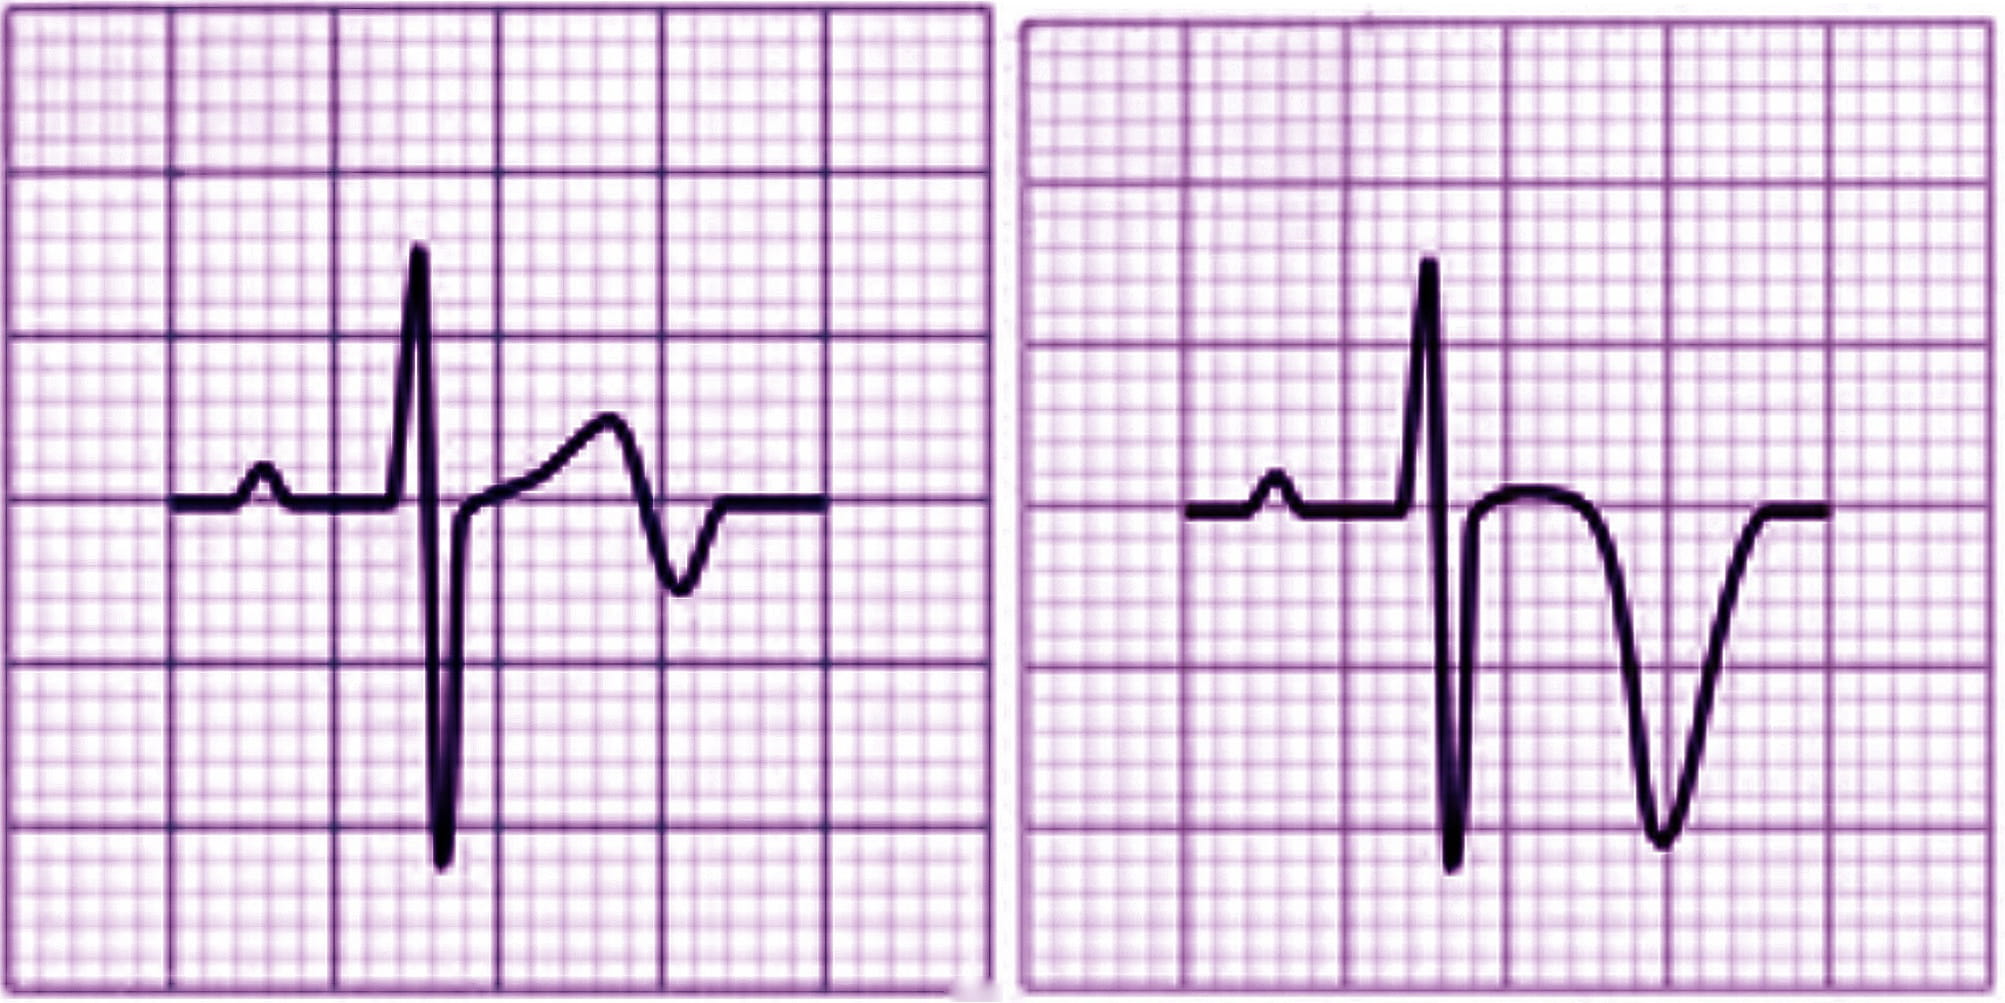

The ECG conducted in the emergency department (Fig. 2 — admission ECG) revealed sinus tachycardia with a heart rate of 103 beats per minute. Poor progression of the R wave in the precordial leads was observed along with minimal ST segment elevation from V1 to V3 in the context of widespread ventricular repolarization abnormalities.

Fig. 2.

Fig. 2.Admission ECG showing sinus tachycardia with a heart rate of 103 beats per minute. Poor progression of the R wave in the precordial leads was observed along with minimal ST segment elevation from V1 to V3 in the context of widespread ventricular repolarization abnormalities. ECG, electrocardiogram.